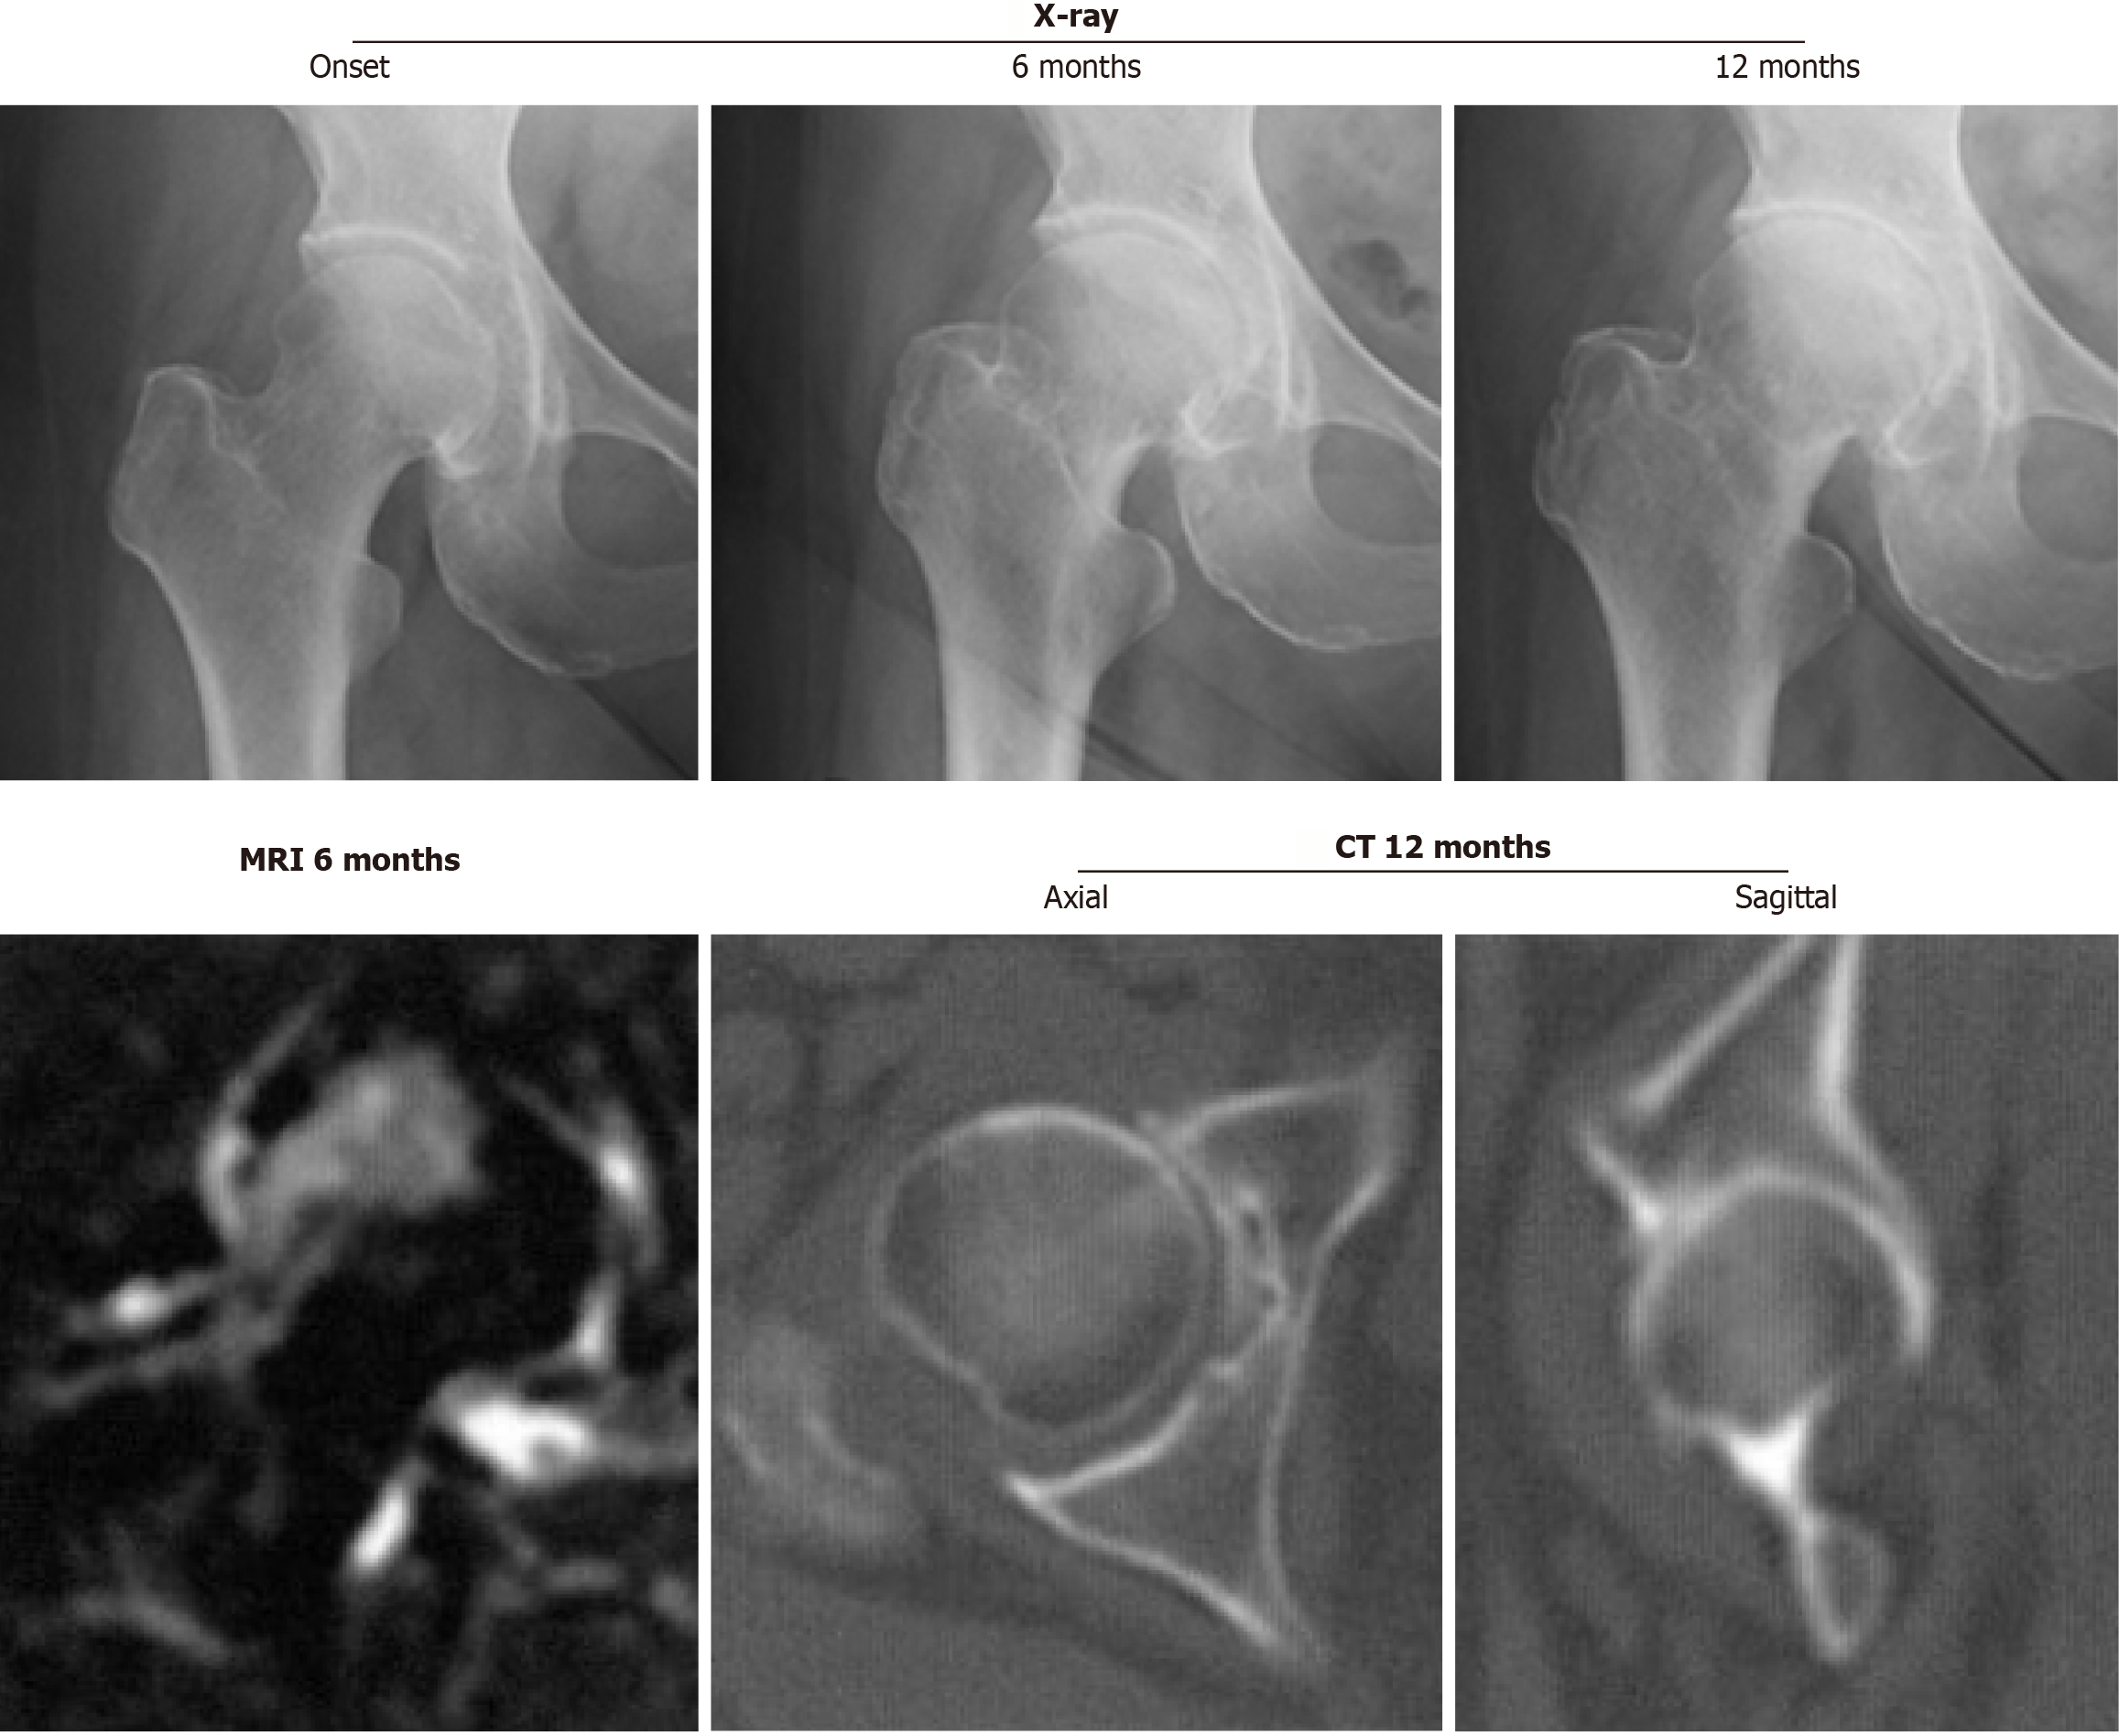

Figure 3

Right hip joint with subchondral insufficiency fracture of the femoral head showing fracture on the subchondral area in the superolateral portion of the femoral head without joint space narrowing.

CT: Computed tomography.